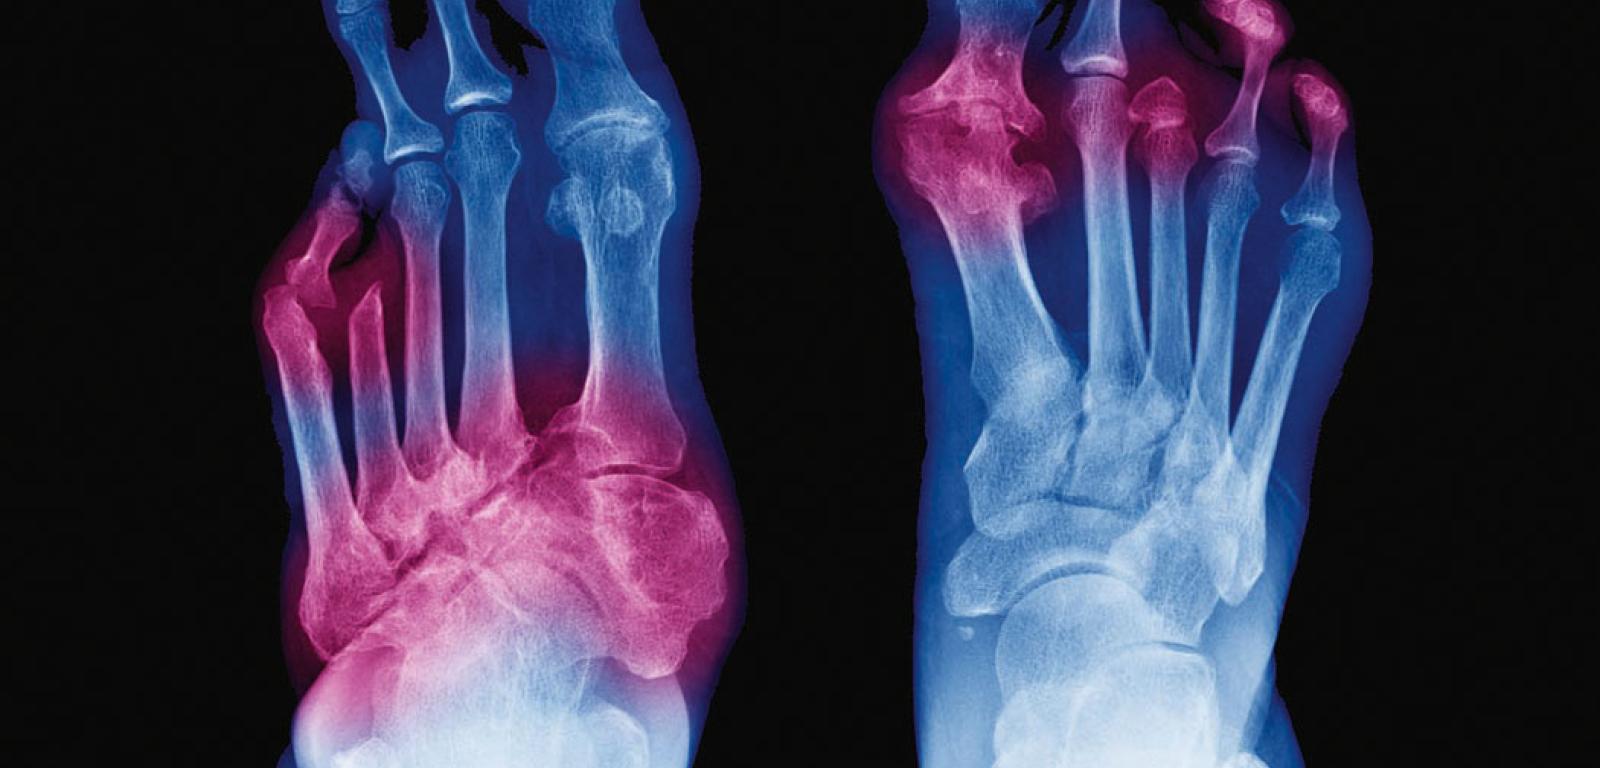

Martwica tkanek w zespole stopy cukrzycowej. Zdjęcie rentgenowskie. Różowe obszary – zajęte stawy.ChooChin/Shutterstock Martwica tkanek w zespole stopy cukrzycowej. Zdjęcie rentgenowskie. Różowe obszary – zajęte stawy.

Przewlekłym powikłaniem cukrzycy jest także zespół stopy cukrzycowej, kończący się niekiedy amputacją kończyny dolnej. Zaburzenia ukrwienia i czucia bólu sprawiają, że pacjent przez pewien czas nie zauważa skaleczenia stopy, w wyniku czego dochodzi do zakażenia, a upośledzone ukrwienie powoduje osłabienie odpowiedzi immunologicznej w obrębie tkanek i utrudnia gojenie. Jątrzące się rany i martwica tkanek sprawiają, że nieraz kończyny nie udaje się uratować. Dlatego w przypadku chorych na cukrzycę wyjątkowo ważne jest noszenie wygodnego obuwia, szczególne dbanie o higienę stóp i ostrożne skracanie paznokci, aby nie doprowadzić do skaleczeń.